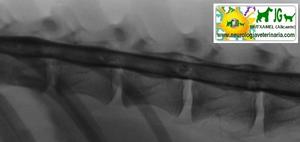

![]() por Juan M. Griñán. Veterinario ![]() comparativa entre una mielografía (mostrando la aguja) y una resonancia magnética, secuencia SE T1w (mostrando donde está el saco dural, sitio para la inyección del contraste). Nótese la extravasación del contraste yodado en la mielografía. | |||||||||